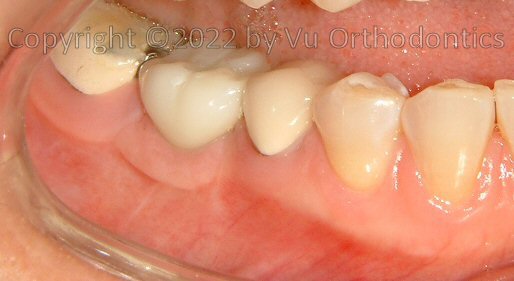

For many patients, the posterior of the lower arch needs Free Gingival Graft (FGG) because of poor quality of keratinized mucosa. The case, infra, shows as an example.

Fig. 10. Poor keratinized mucosa on the buccal side of the implant (with healing abutment)